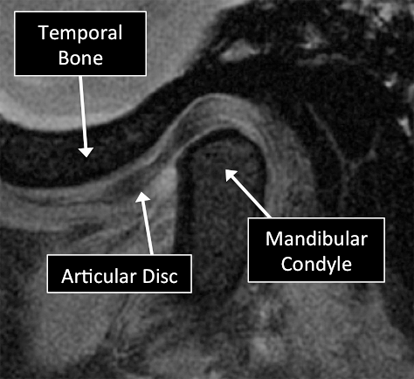

What is MRI used for in the TMJ?

MRI can visualize many of the different structures in the TMJ. Certain diseases affecting those structures can be diagnosed using MRI. Common diseases include abnormal position, tears and degeneration of the articular disc, osteoarthritis, tumors, among others.

MRI examinations showing normal (top) and abnormal (bottom) TMJ.

Why Translational MRI of the TMJ?

In the TMJ, as in many other parts of the body there is certain structures that can’t be seen with the standard MRI used in the clinical practice. There are new techniques that allow the visualization of some of the structures which are otherwise “invisible” in the standard MRI. Some of these “invisible” structures are unique to the TMJ (articular disc) and other are found in other parts of the body (e.g. tendons, ligaments, cortical bone).

TMJ MRI examinations using the standard MRI techniques (top) and translational MRI techniques (bottom).